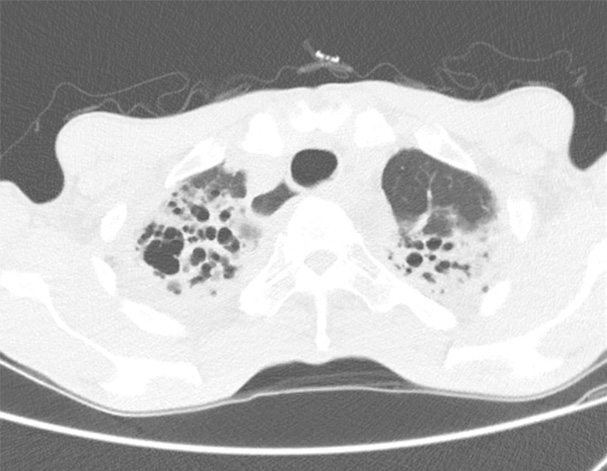

기관지확장증의 CT 사진